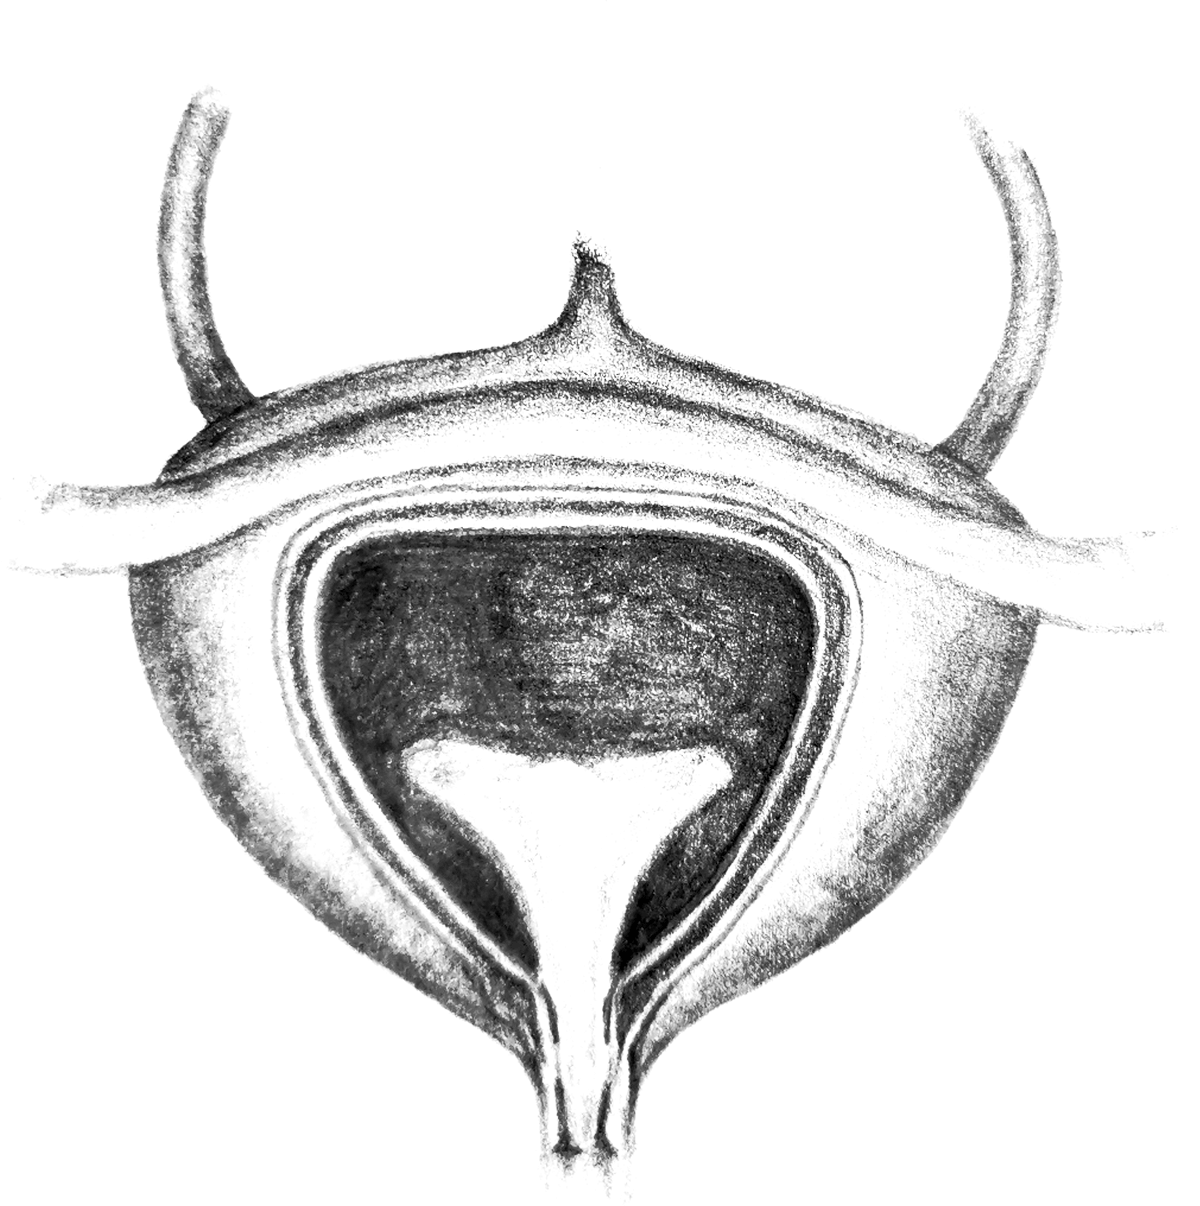

Die Harnblase befindet sich im unteren Teil der Bauchhöhle. Sie ist ein Hohlorgan und von Muskulatur umgeben. Bei Frauen ist die Harnröhre sehr kurz. Deshalb können Bakterien leichter als beim Mann über den Harnleiter in die Blase gelangen. Das kann beispielsweise beim Toilettengang passieren. Eine schmerzhafte Blasenentzündung kann die Folge sein, wenn Bakterien wie Escherichia coli aus dem Darmbereich in die Blase wandern. Bei dem entzündlichen Prozess wird unter anderem die Blasenschleimhaut angegriffen. Auch Stress und andere Faktoren können die empfindliche Blase beeinträchtigen, in deren Umfeld viele Nerven angesiedelt sind. Verschiedene natürliche Stoffe fördern die Blasenfunktion, unterstützen die Regeneration der Blasenschleimhaut und können bei einer Blasenentzündung Wohlbefinden stärken, sowie Erholung fördern. Wir stellen Ihnen hier einige wichtige Substanzen vor, die Sie als Nahrungsergänzungsmittel für die Blase zu sich nehmen können.